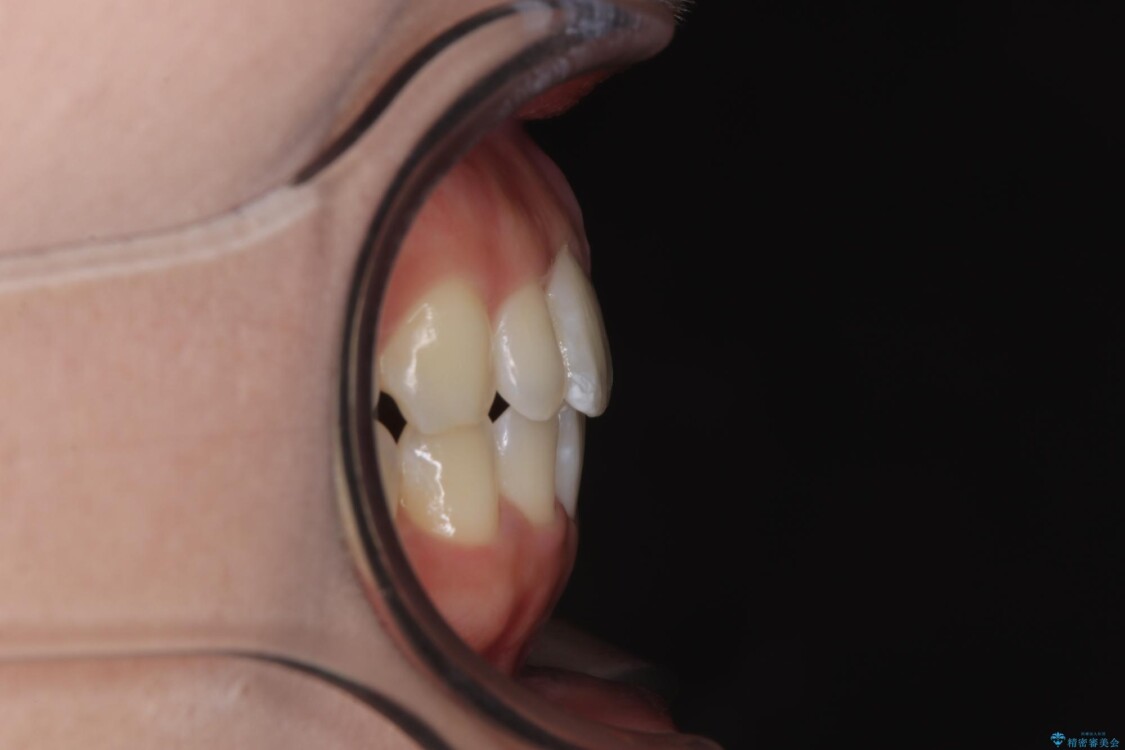

歯列アーチが狭くスペース不足により前歯がデコボコしている状態でした。見た目を改善しつつ、前歯を前方に突出させず、自然な笑顔を目指したいというご希望でした。

・アーチを側方に拡大して歯が並ぶスペースを確保

・抜歯は避け、非抜歯での対応

治療前

治療途中

• 目立ちにくい表側装置で1年完了!狭いアーチを側方拡大し前歯のデコボコを整えた症例 治療途中画像